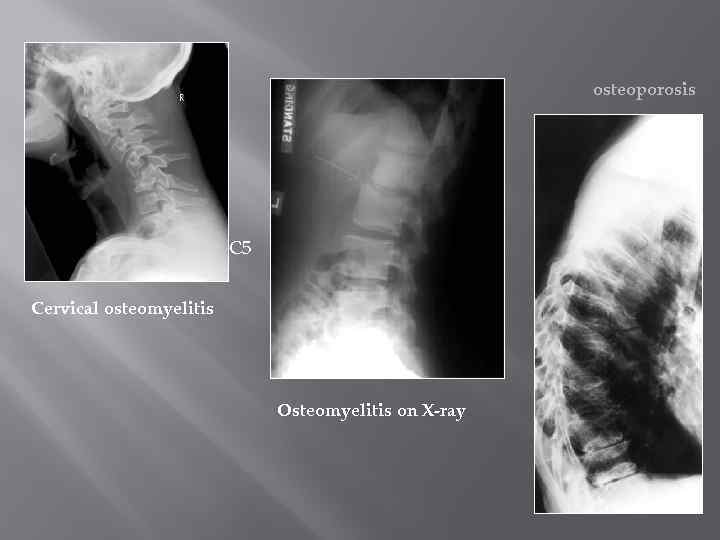

Спондилография Проекции: профильная / боковая косые прицельные снимки отдельных позвонков томография изменения в позвонках, сочленениях и связочном аппарате врожденные дефекты изменения позвоночного столба ДДЗП Воспалительные заболевания Травмы опухоли 32

osteoporosis C 5 Cervical osteomyelitis Osteomyelitis on X-ray